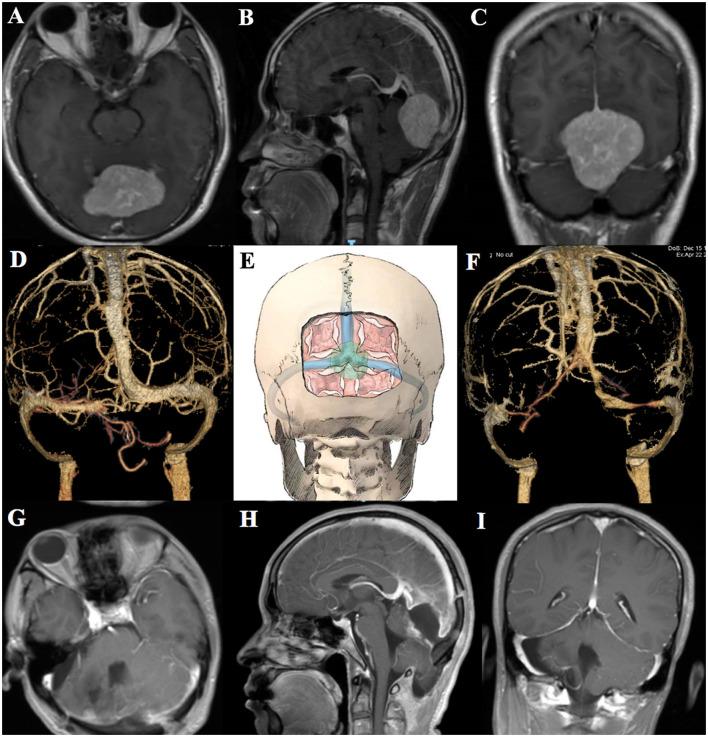

All patients underwent surgeries in the prone position, and occipital/sup-occipital/sub-occipital craniotomy was performed. In one patient, the skull was removed traditionally with exposure of the confluence of sinuses, superior sagittal, and transverse sinus, while the longitudinal skull bridge was left to suspend the dura for protecting the superior sagittal sinus in one patient, and the transverse skull bridge was left to suspend the dura for protecting the transverse sinus in one patient. The dura was opened infratentorially or supratentorially to spare the sinus and then the "skull bridge" was suspended. The tumor was then removed completely without brain swelling or significant venous bleeding. Complete tumor resection was confirmed by early postoperative imaging, and all patients recovered well without postoperative morbidity.

The authors recommend the "skull bridge" to suspend the dura for optimal control of the venous sinuses during FM surgery (less venous bleeding).